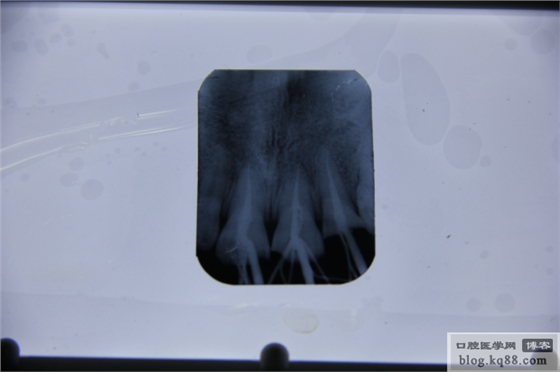

感覺還可以,說明宇森的根測測量的很準(zhǔn)。再看看根充以后的片子。

發(fā)現(xiàn)一個不該犯得的錯誤,髓室居然沒有完全打開。再看看從始至終的片子吧!

很多時候我們在追求精致,完美;其實(shí)完美有時候可以很簡單;精致亦然,人生亦然。機(jī)器好不好,用了才知道,物美價廉,功能強(qiáng)大。根管治療的好幫手。支持民族品牌。